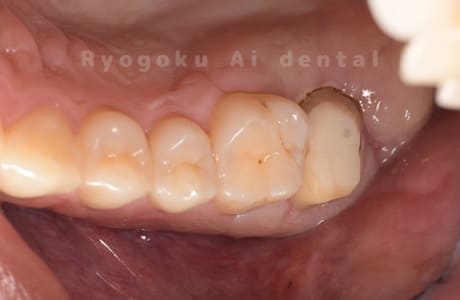

Case21

-

- 原因

- 重度カリエス

- 治療内容

- クラウンレングスニング

- 治療費用

- 44,000円

他院で抜歯と宣告され、当医院を受診された患者様です。クラウンレングスニングを行い、保存を行いました。経過良好です。

<リスク・副作用>

手術後は痛み、腫れ、痺れ、青あざなどの副作用が生じます。痛みは痛み止めを処方しますが、腫れ、青あざは1週間程度生じる場合があります。また、部位によっては神経の走行が複雑で、痺れが残り、長期的にお薬を処方する場合があります。